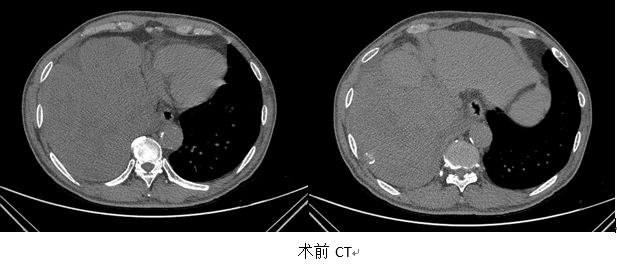

患者为63岁的上海本地男性,8年前,曾因罕见的男性乳腺癌做了手术,6次化疗后恢复不错。可是,3年前的一次例行复查中,他发现右胸腔有一个肿瘤,报告显示良性可能大,因此也未引起足够重视。1个月前,患者出现胸闷、气短,伴有咳嗽,CT检查发现,右胸腔的这一肿瘤明显增大,几乎占据了整个胸腔的75%,且右中、下肺已被肿瘤挤压到失去了功能。更可怕的是,肿瘤还在快速发展——短短1周内,患者出现大量胸腔积液,呼吸出现困难,生命危在旦夕。

争取手术切除,还是取活检做相应辅助治疗?如果进行手术,则需面临很大风险,巨大的肿瘤与肺门血管已没有明显界限,切除肿瘤过程中,可能出现难以控制的大出血,即使解决了出血问题,手术要同时切除失去功能的右中、下肺叶,术后发生呼吸衰竭的风险明显增大;另外,患者还有顽固的低钾血症,围手术期极易出现心血管方面的意外。但如果只做穿刺活检,只能明确肿瘤性质究竟是不是乳腺癌转移病灶,却无法解决患者的呼吸问题。